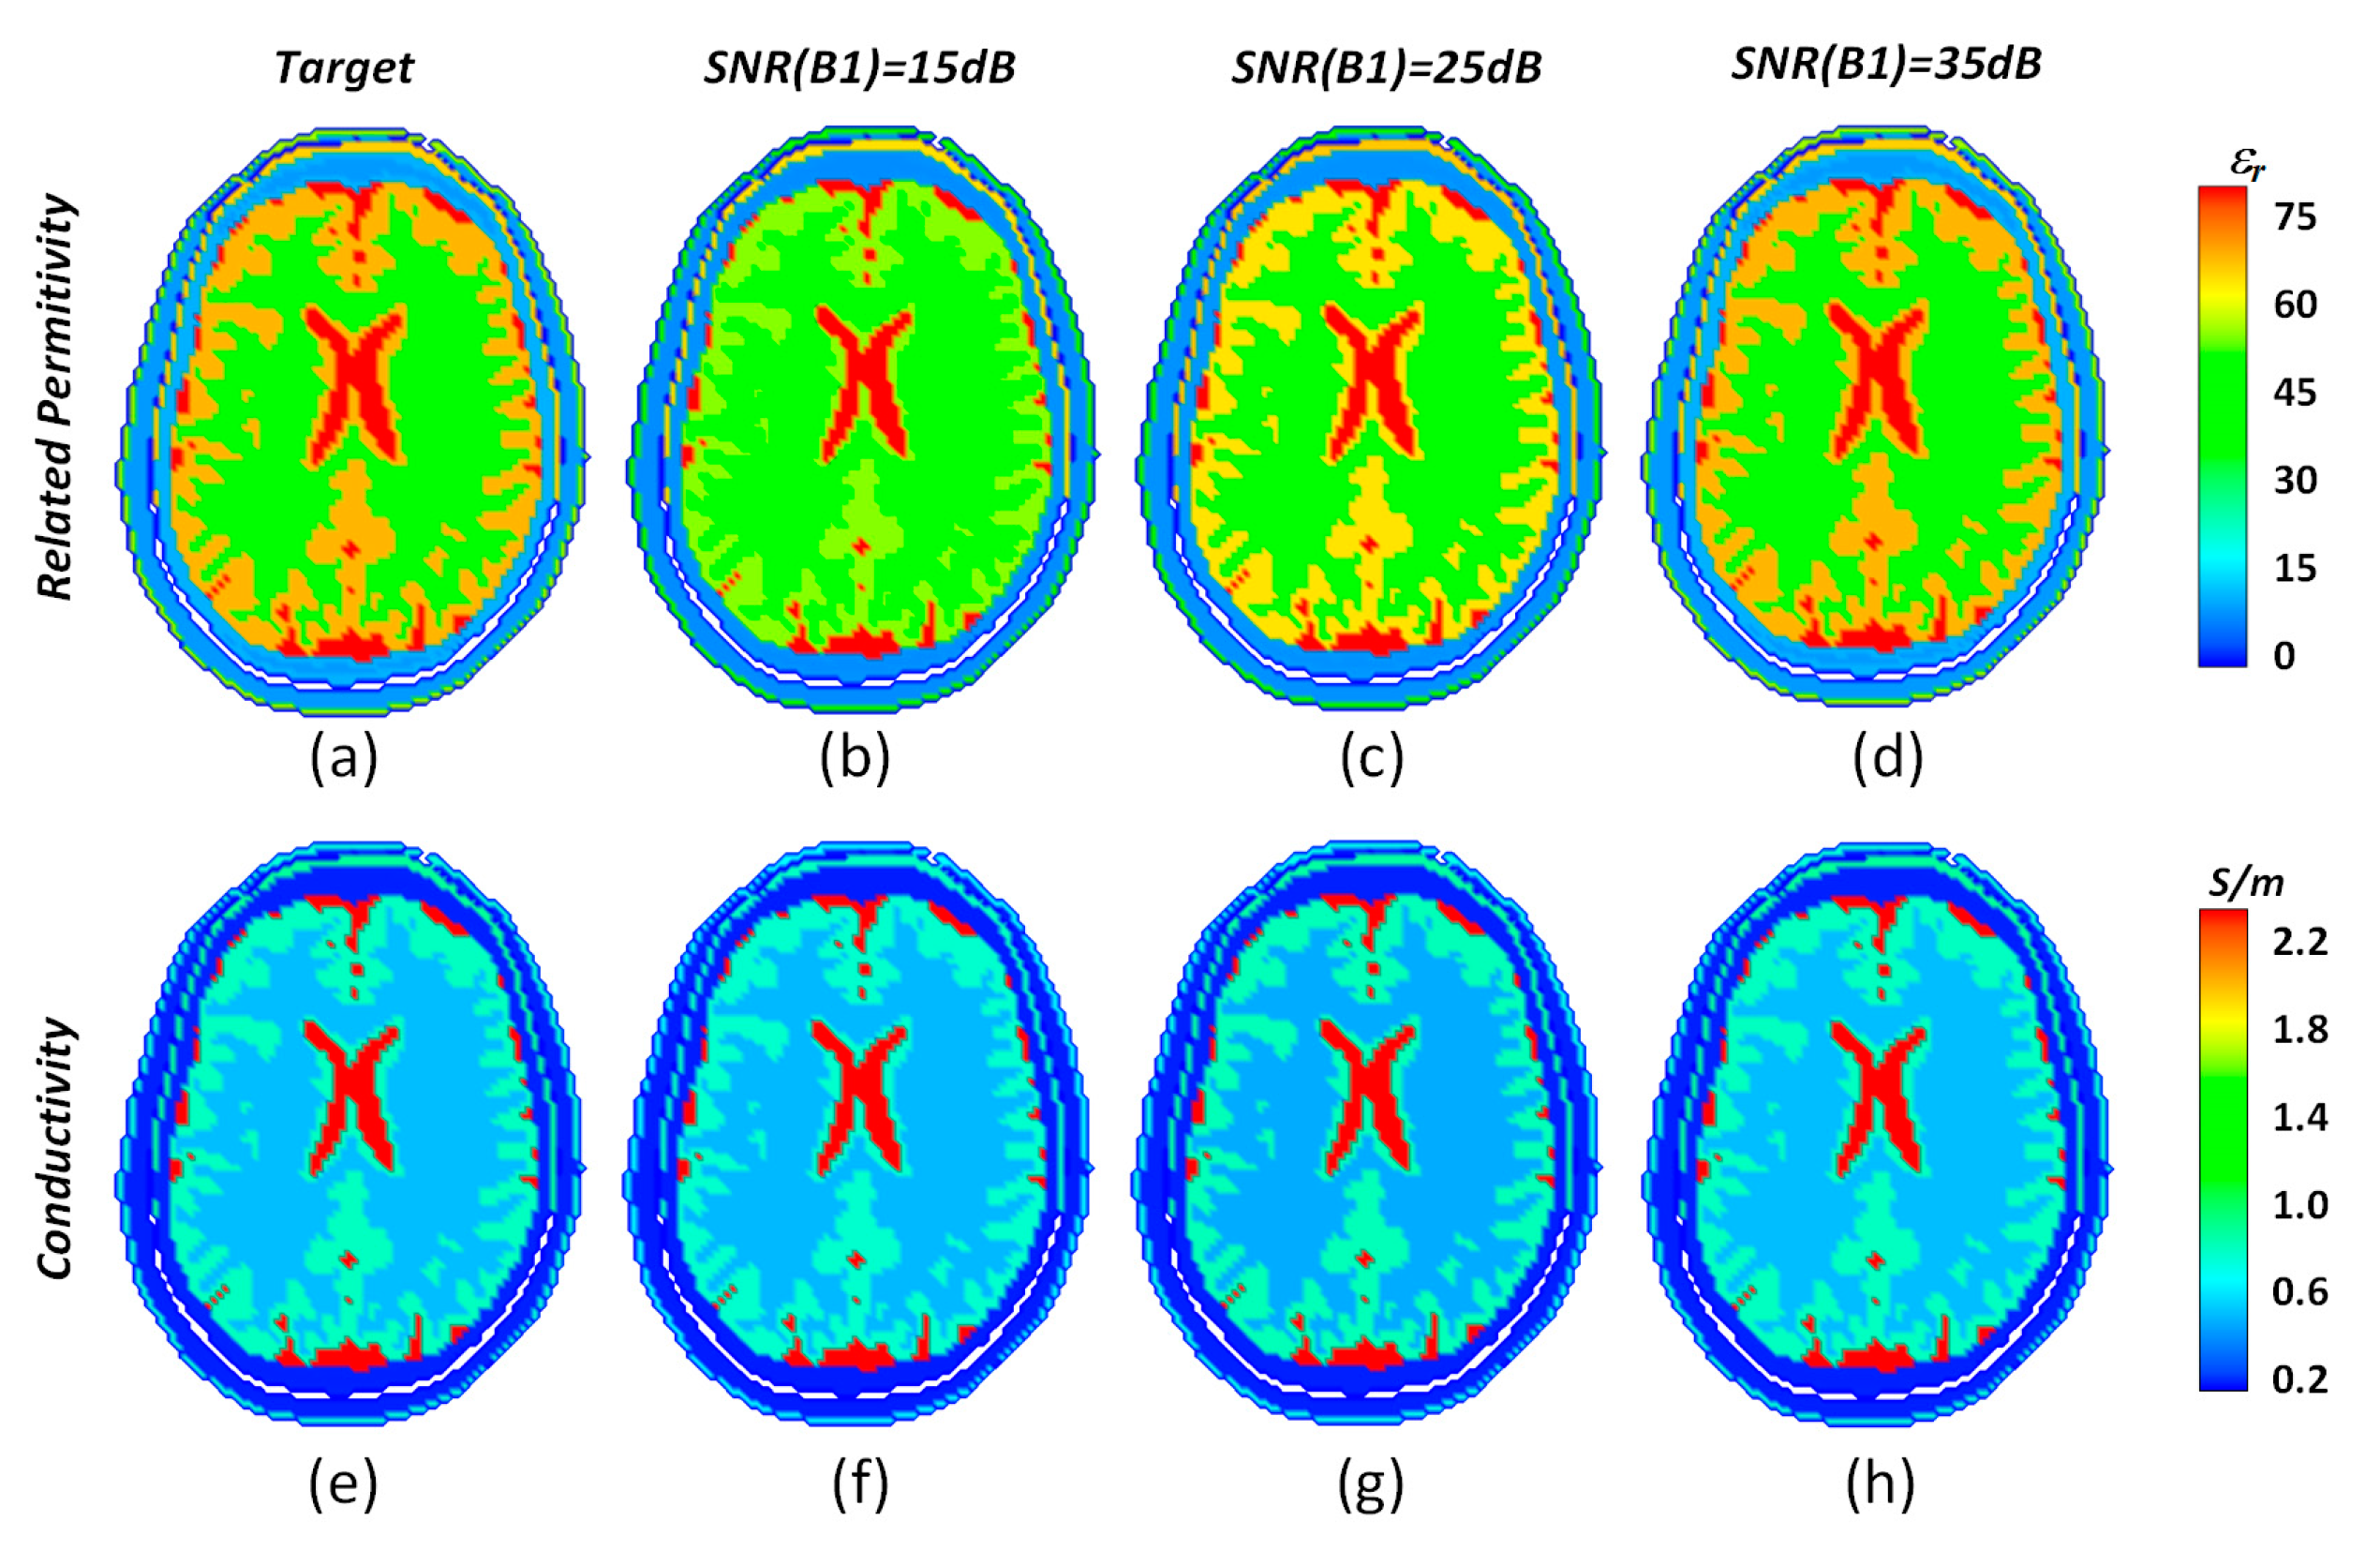

| SNR | Inner | Outer | ||

|---|---|---|---|---|

| εr | σ(S/m) | εr | σ | |

| Target | 78.5 | 0.43 | 78.5 | 0.78 |

| Noise-free | 78 | 0.4309 | 78 | 0.7784 |

| SNR = 15 | 77 | 0.4428 | 79 | 0.7644 |

| SNR = 25 | 77 | 0.4212 | 78 | 0.7918 |

| SNR = 35 | 78 | 0.4278 | 78 | 0.7843 |

| SNR = 45 | 78 | 0.4326 | 78 | 0.7762 |

| SNR = 55 | 78 | 0.4322 | 78 | 0.7824 |